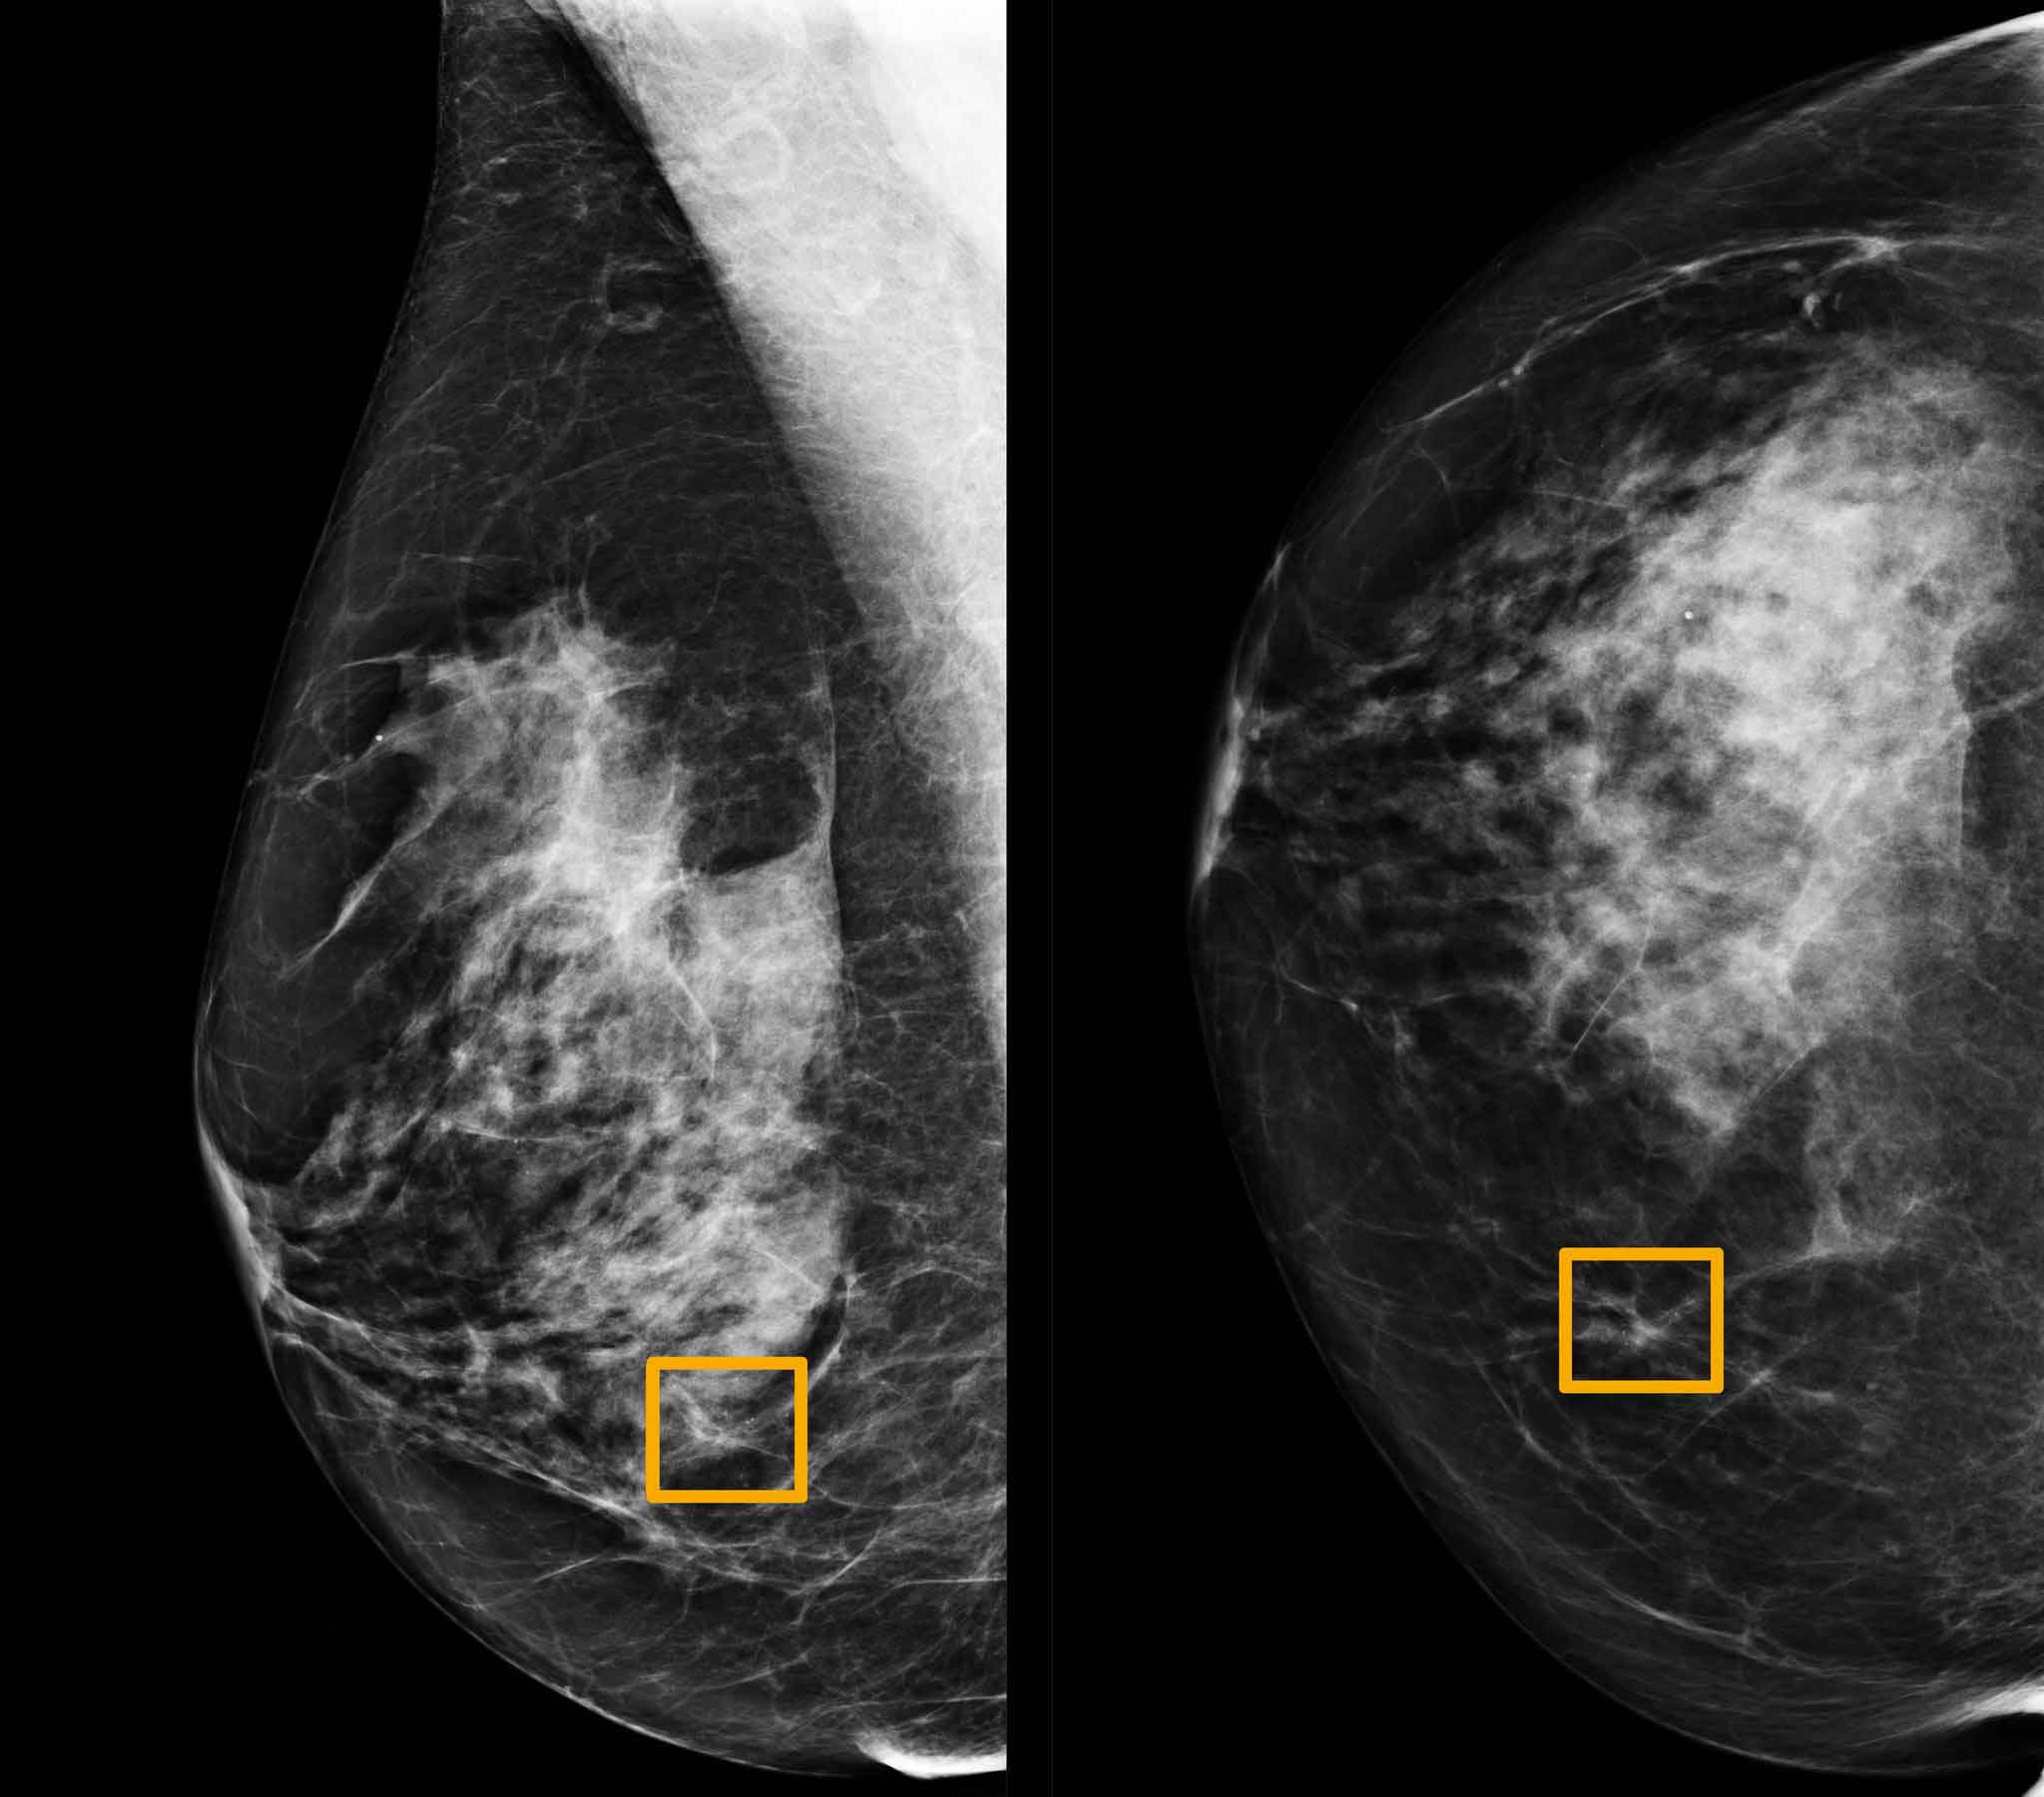

3- ماموگرام

پزشک ممکن است درخواست عکسبرداری با اشعهی ایکس بدهد تا بتواند تشخیص بدهد توده خوشخیم است یا بدخیم.